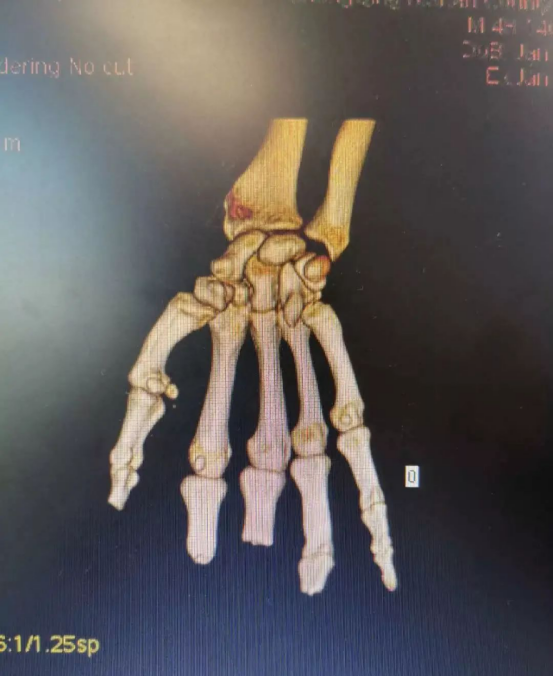

患者陳先生在工廠上班時不慎被沖床沖壓右手,被送到醫院時,整只手血肉模糊,肌腱、血管外露。診斷結果為4指毀損離斷傷,已經無法直接再植,需要“切腳趾、補手指”。

“缺多少、補多少,缺多少、切多少,對于再造手術,我們在關注創面修復的同時,也需要對供區進行關注。不光要注重改善手部功能,還要盡可能減少足部供區的損傷。”主刀醫生胡明興說,考慮到患者對術后恢復效果預期高,經過與患者及家屬溝通,科室團隊決定利用3D打印技術,通過數字化精準設計,輔助手指再造。

在放射科的支持下,醫院對患者雙手進行了CT三維重建,通過技術處理,虛擬出了患者缺失的手指,再使用新型材料打印出3D模型,模擬患者的斷指。通過對3D模型進行設計取樣,對患者右拇指、中指精準再造。

手術過程順利,由于3D打印技術的精準化輔助,兩根再造的手指外形美觀,不需要進行二期整形修復,足部供區創傷也達到最小化。又能用右手寫字、吃飯,陳先生很高興,“等這兩根手指恢復得差不多了,我馬上就來修復剩下兩根手指!”